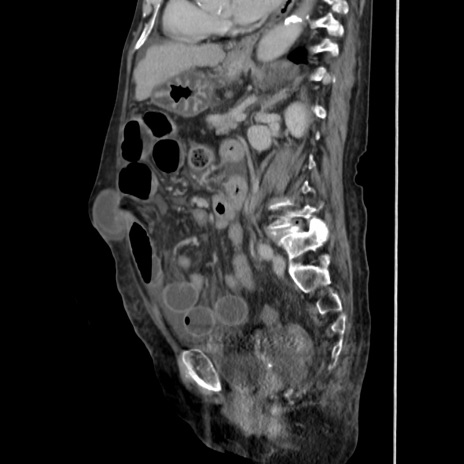

症例31(矢状断像)

【症例】80歳代 女性

【主訴】腹部膨満感

【現病歴】他院にて肝硬変にてフォロー中。1週間前から便秘、腹部膨満感、臍部腫瘤あり受診となる。

【既往歴】肝硬変

【身体所見】腹部膨隆あり、皮膚変化なし、疼痛なし。

【データ】WBC 4600、CRP 0.25